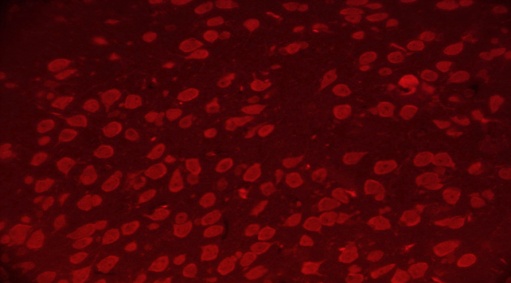

TEL increased NeuN expressions in MPTP intoxicated mice brain

SNpc and ST regions of MPTP mice brain showed a significant decrease in % NeuN immunopositive cells [F (4,10) = 274.1, p<0.01 and F (4,10) = 86.24, p<0.01, respectively] when compared to the vehicle treated mice. TEL (3 and 10 mg/kg) significantly (p<0.01) increased % NeuN immunopositive cells in both the regions in comparison to MPTP mice (fig. 4).

Fig. 4: Effect of TEL on % NeuN immunopositive cells in MPTP intoxicated mice brain. Pictures represent NeuN immunopositive cells of (A) SNPc and (B) ST brain regions X 400 magnification. (1) Normal control, (2) MPTP induced mice brain, (3) TEL (3 mg/kg b. wt.) administered MPTP mice brain, (4) TEL (10 mg/kg b. wt.) administered MPTP mice brain and (5) TEL (10 mg/kg b. wt.) administered normal mice brain. (C) Values were expressed in mean±SEM, n=4 animals/group, statistical analysis was performed using one way ANOVA followed by Tukey’s multiple comparison test, ## indicates p value<0.01 Vs group I, ** indicates p value<0.01 Vs group II